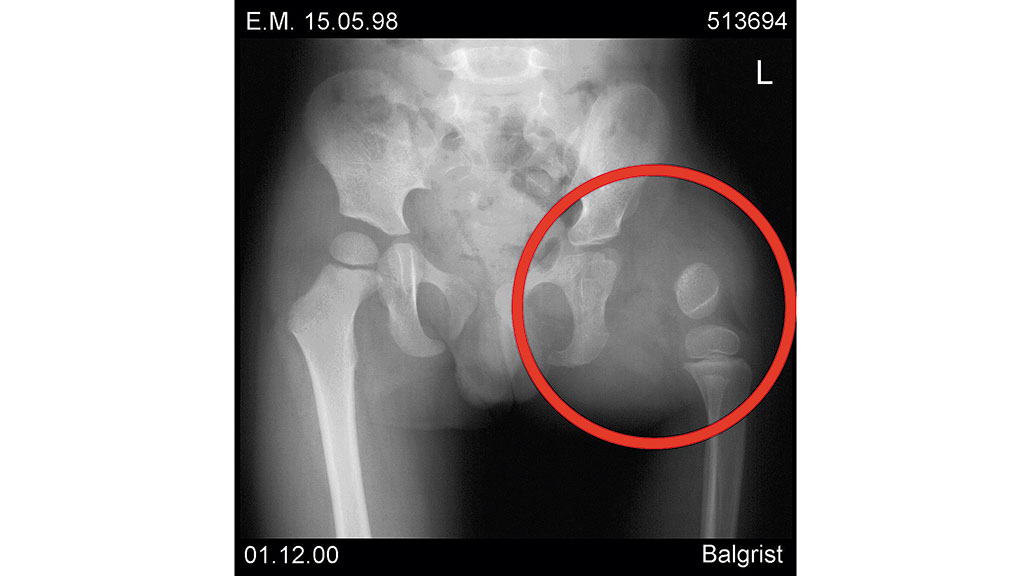

Im zweiten Fall handelt es sich um ein 8‑jähriges Mädchen, das infolge einer intrauterinen Embolie (im 7. Schwangerschaftsmonat) nach der Geburt transfemoral amputiert wurde. Das Erscheinungsbild des Stumpfes wirkt äußerlich wie ein Knie-Exartikulationsstumpf (Abb. 8). Am distalen Femurende waren mehrere Knochensegmente eingelagert, die die Patientin muskulär bewegen konnte (Abb. 9). Das Hüftgelenk wurde zu Beginn der Versorgung mit 10 Monaten als nicht stabil eingestuft.

Mit fünf Jahren fusionierte man die einzelnen distalen Knochensegmente mit einer Schraube, die man nach einem halben Jahr entfernte (Abb. 13). Seither wird die Patientin mit längsovalen Schäften (M.A.S.) versorgt (Abb. 14). Die dafür verwendeten Fuß- und Kniepassteile brachte die Patientin in kürzester Zeit mit Defekten zurück, besonders die Vierachskniegelenke mit Federvorbringer. Bei der derzeitigen Versorgung nutzten die Orthopädie-Techniker ein einachsiges Kniegelenk mit Hydraulik und den Pediatric-Prothesenfuß (Abb. 15).